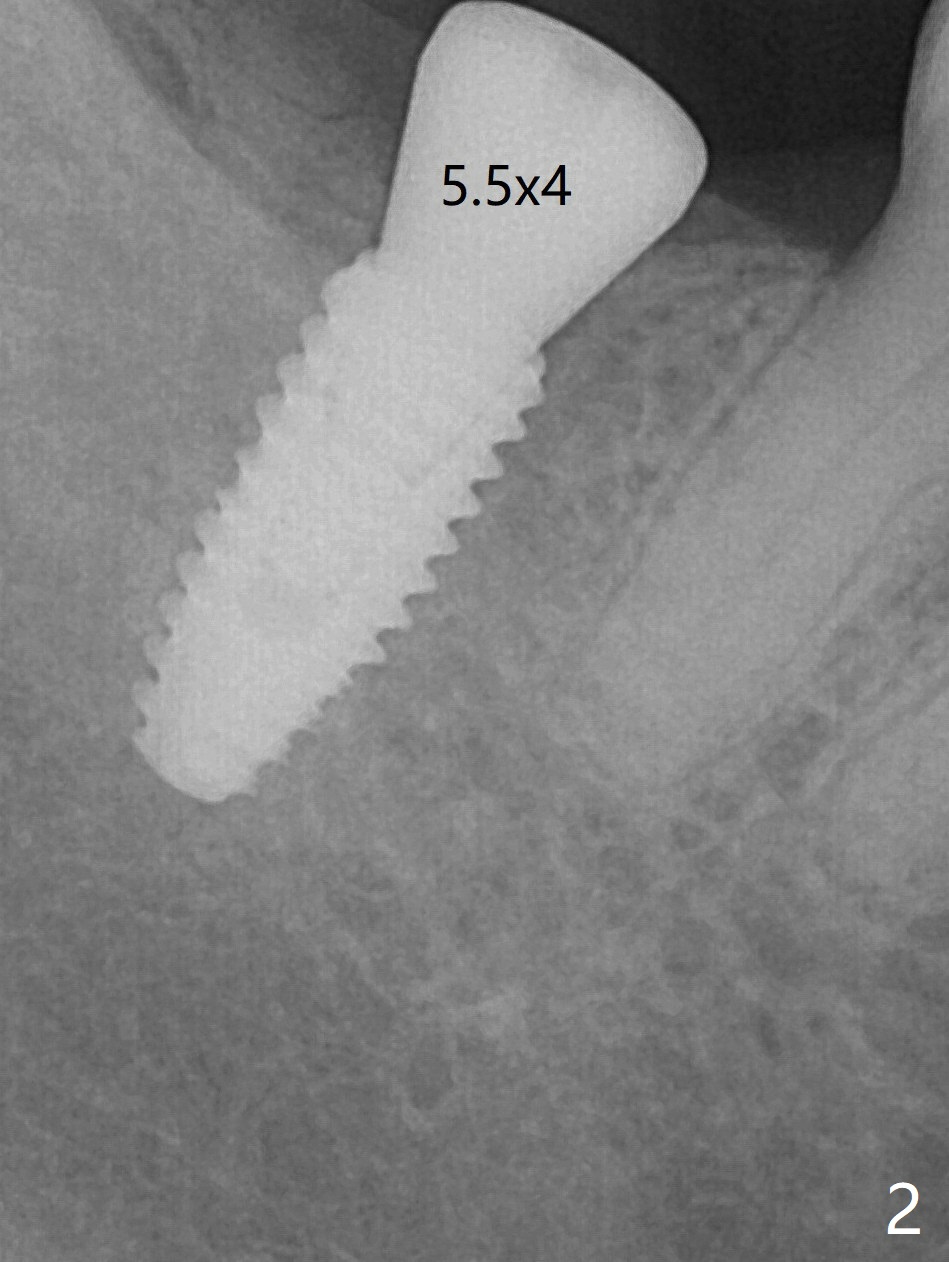

After placement of a 4.5x10 mm implant with guide at #31 and before placement of a 6x4 (Fig.1) and finally a 5.5x4 (Fig.2) mm healing abutment, a 5.7x5(2) mm dummy (planning) abutment is placed without restorative space. It appears that either orthodontic or restorative intrusion is necessary. The patient prefers the latter. The reasons of switching the large healing abutment to the smaller one are two-folded. The primary stability of the implant is ~ 10 Ncm. Tongue mobility may cause fibrointegration. The 6 mm abutment seems to contact the mesial crestal bone (Fig.1). In fact the smaller abutment does not help much. It may be related to radiation angulation. A smaller sensor will be used to reduce the angulation 3-4 months later. In fact #1 sensor does produce better image with less angulation (Fig.3). After trimming a 5.2x4.5(3) mm abutment and opposing tooth (palatal cusp), impression is taken.